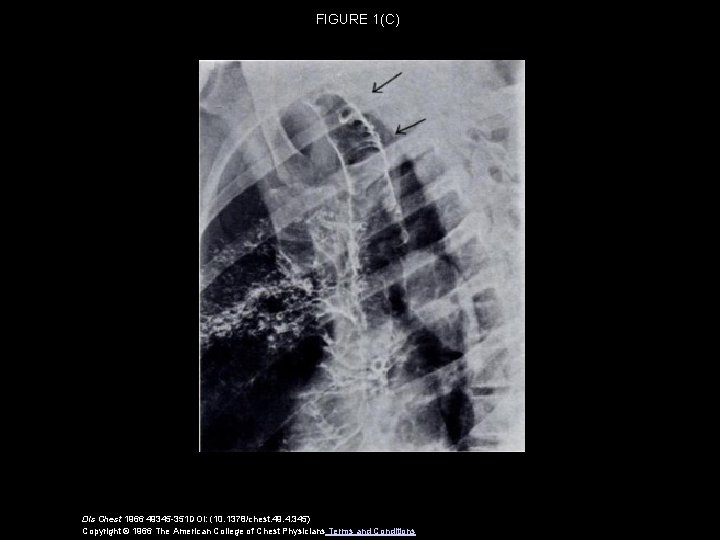

FIGURE 1(C) Dis Chest 1966 49345 -351 DOI: (10. 1378/chest. 49. 4. 345) Copyright © 1966 The American College of Chest Physicians Terms and Conditions